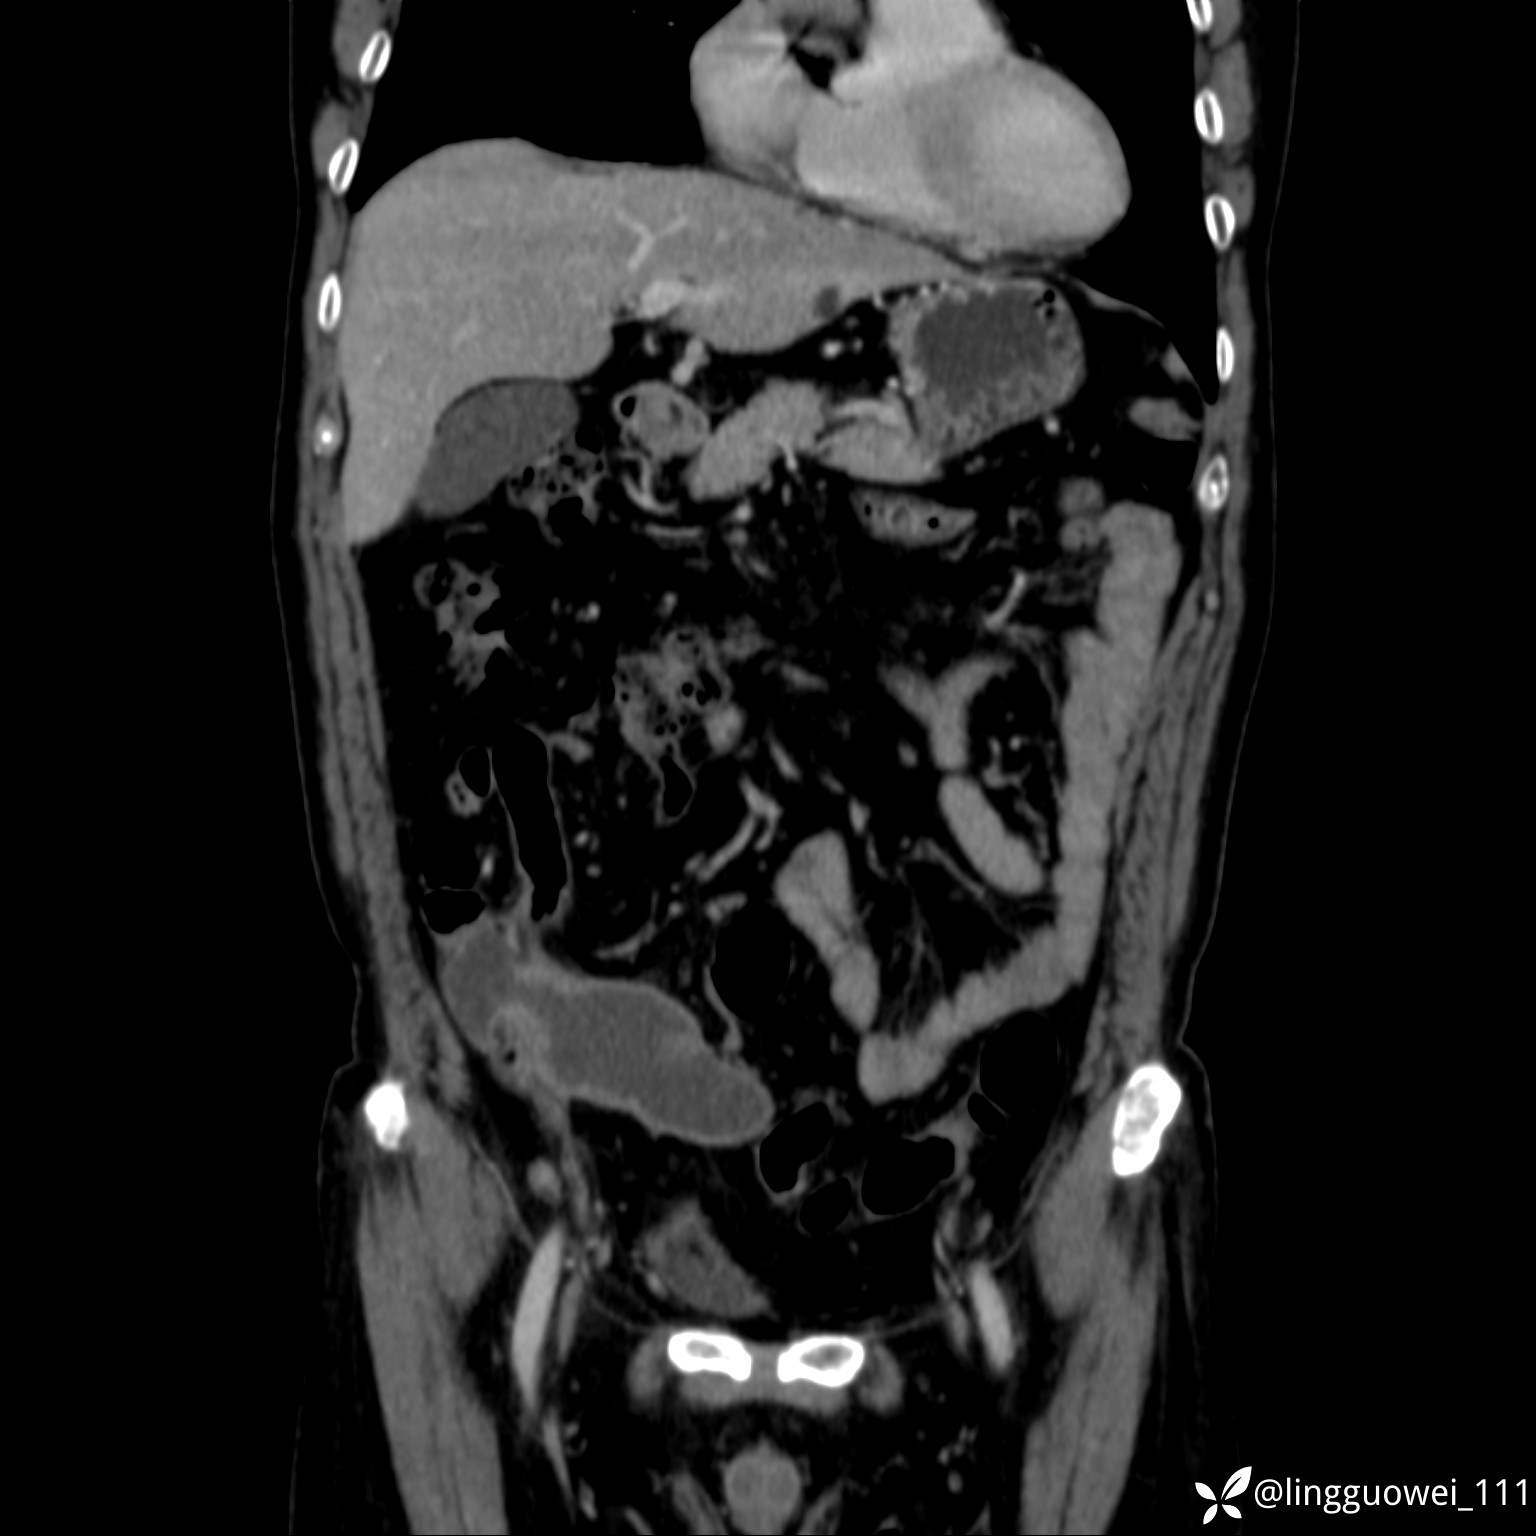

62岁,男,2天前无明显诱因出现下腹部疼痛不适,呈持续性,程度稍剧,同时伴有尿频、尿急及尿不尽感,无畏寒、发热。

平扫: